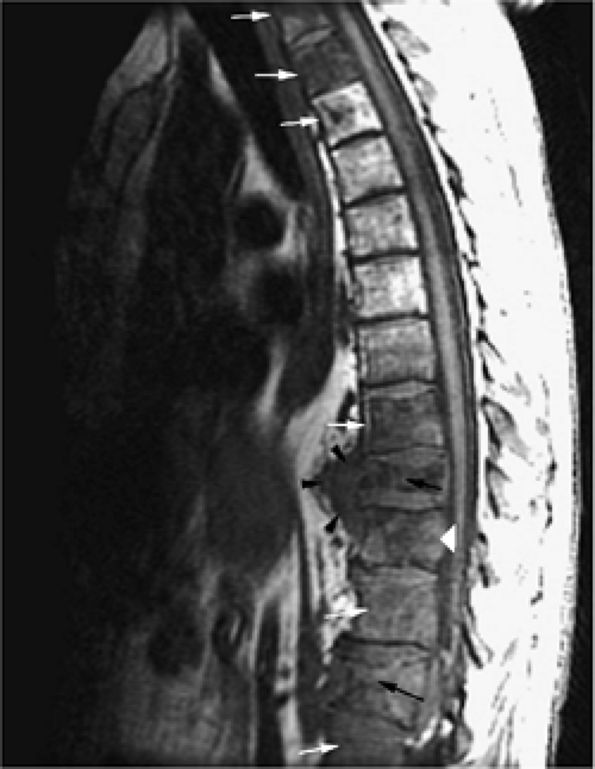

|

FIGURE 13.67 ● Metastatic lung carcinoma. Baseline study shows metastatic disease of the upper thoracic spine (arrows). (A) Metastases are hypointense on a sagittal T1-weighted image. (B) Enhancement following the administration of intravenous gadolinium is noted on a sagittal fat-suppressed T1-weighted image. (C) Metastatic tumor is hyperintense on the corresponding STIR image. Follow-up study demonstrates marked progression of metastatic disease (arrows). (D) Metastatic marrow infiltration is hypointense on a sagittal T1-weighted image. Pathologic compression fracture (white arrowhead) shows convex posterior vertebral body cortex. Mediastinal tumor infiltration (black arrowhead) is noted. (E) On a sagittal contrast-enhanced fat-suppressed T1-weighted image, there is enhancement of metastatic disease. (F) Metastases are hyperintense on a corresponding STIR image.